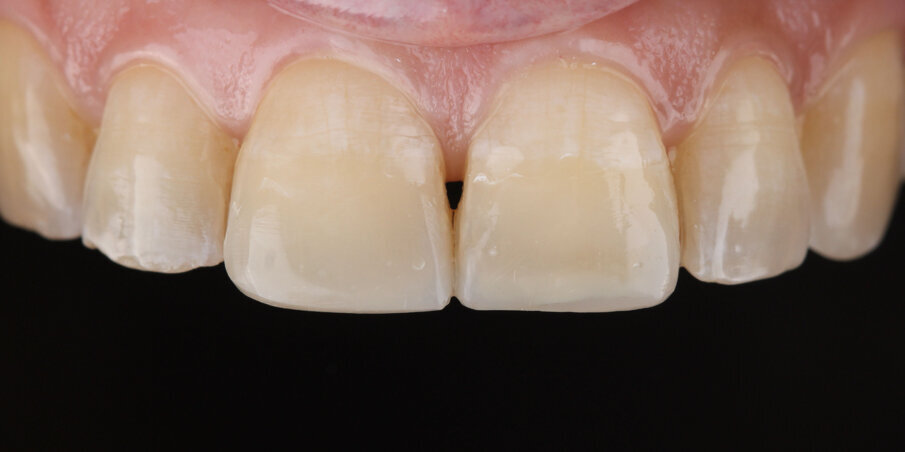

Smile analysis reveals the presence of a reverse smile line giving the patient a slightly senile appearance (Fig 4).

Fig 4: Initial smile